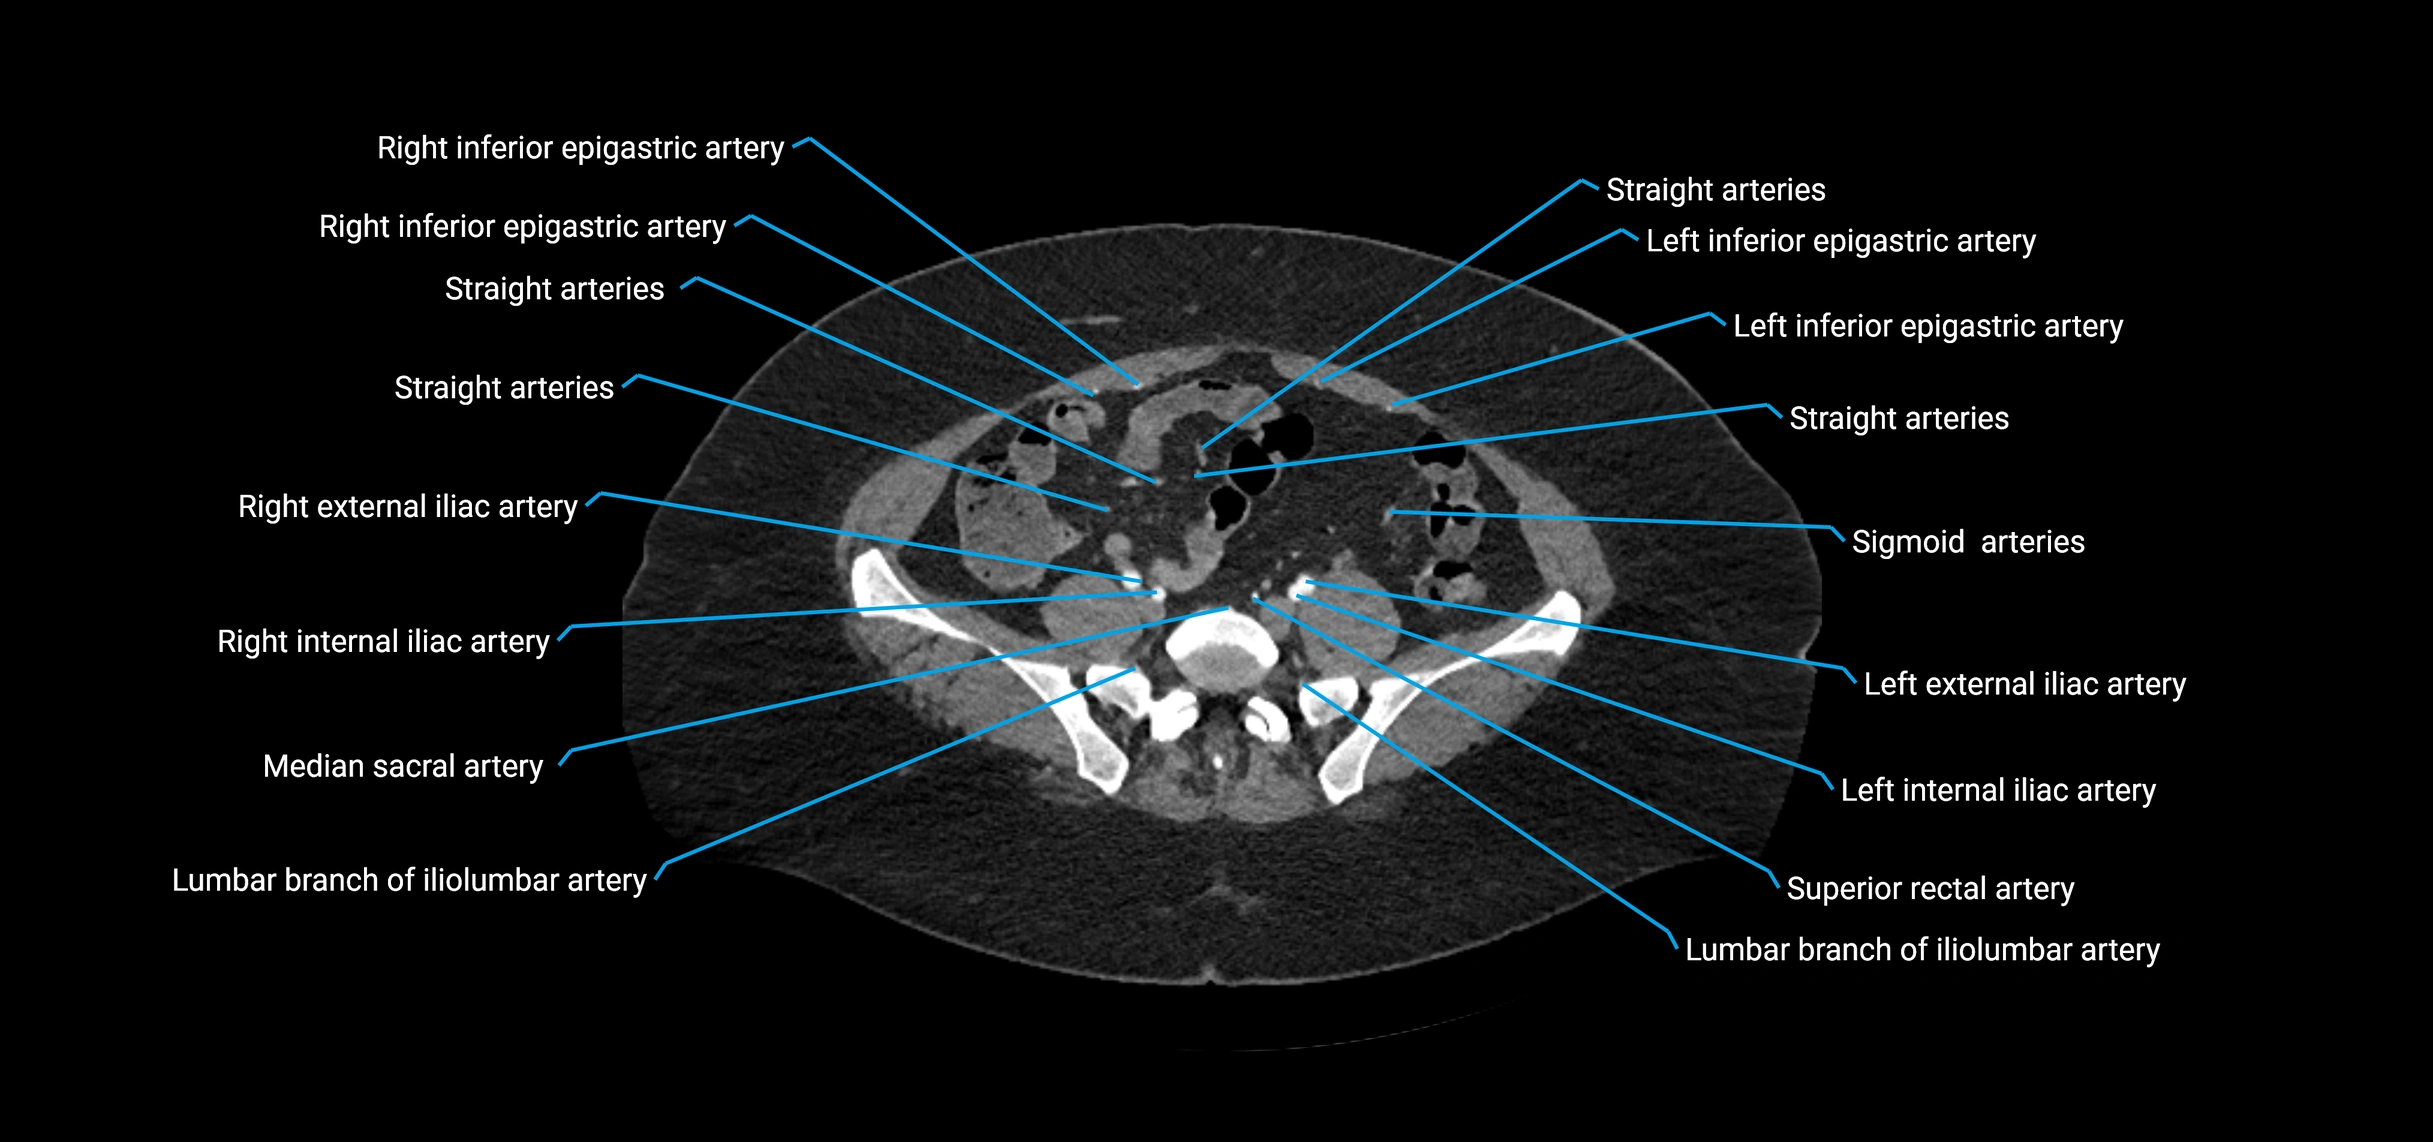

Contrast-enhanced CT (CTA):

• Gold standard for abdominal aortic imaging

• Provides excellent detail of lumen, wall, aneurysm, thrombus, and branch vessels

• Multiplanar and 3D reconstructions help in aneurysm measurement, stent graft planning, and dissection evaluation

• Detects acute rupture, traumatic injury, or occlusion with high sensitivity